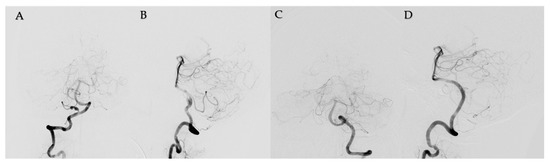

2. Case Report